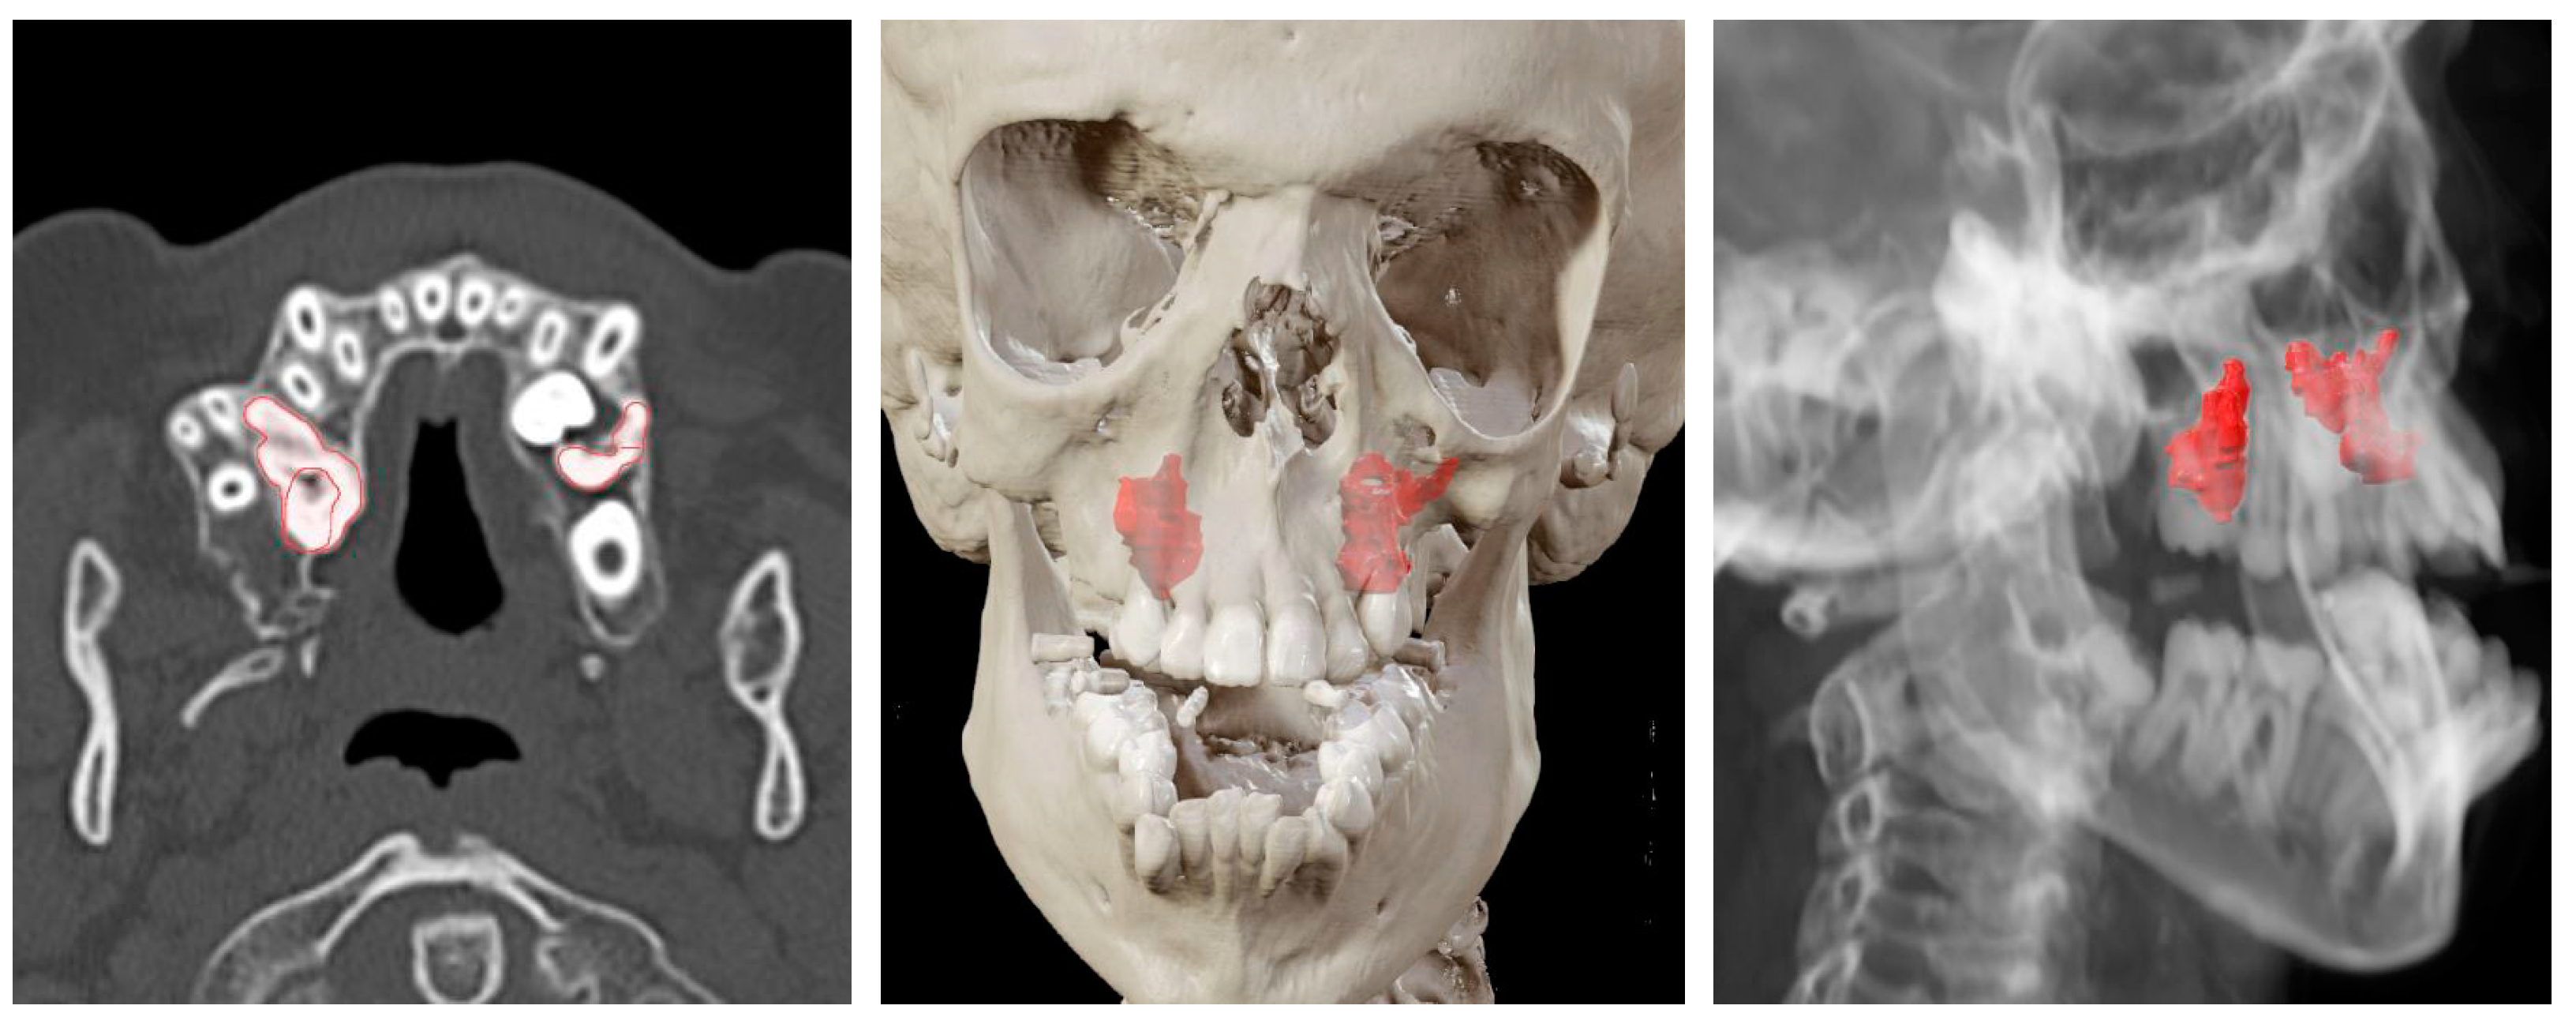

| Case | Target 1 | Target 2 | Target 3 | Target 4 |

|---|---|---|---|---|

| Case 1 Foreign body | 1.00 mm | |||

| Case 2 Impacted teeth in Pfeiffer Syndrome | 0.5 mm | 0.3 mm | 0.6 mm | |

| Case 3 Impacted teeth in Apert Syndrome | 0.3 mm | 0.5 mm | 0.4 mm | 0.5 mm |

| Case 4 Impacted teeth | 0.3 mm | 0.2 mm |